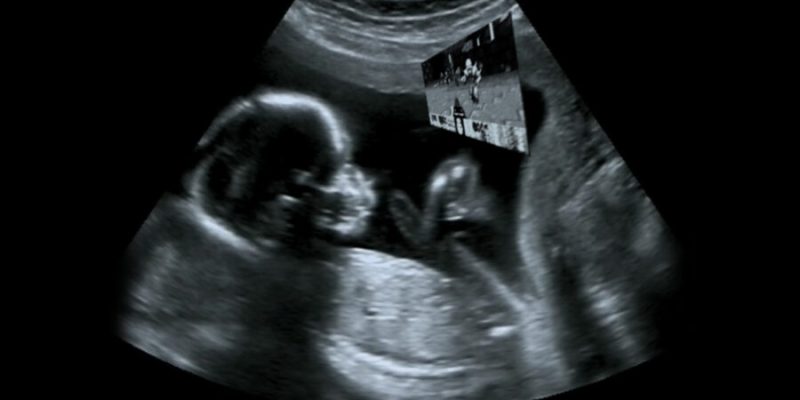

EAST LANSING, Mich. — A group of medical students at Michigan State University have successfully modded an ultrasound machine to allow unborn fetuses to play 1993’s Doom on it, sources have confirmed.

“Oh my god, we did it, we really did it,” said Michael Powers, a medical student that spearheaded the project. “In addition to being fascinated by technology, we’re all huge gamers, so we really wanted to take a crack at doing something cool with Doom. When we first started talking about [hacking the ultrasound machine so fetuses could play Doom] we thought it sounded a little crazy, but the more we thought about it, the more we knew we had to try it.”

“I guess I can appreciate it on some technical level, even if I don’t fully get it, but I didn’t come here to see that crap,” said Sally Baker, a recent visitor to nearby Sparrow Hospital, where the machine is currently in use. “Me and my husband wanted to get a look at the growth of the baby, and maybe even the gender, not see it play Doom! Although, my husband disagrees and says he’s really excited that his first born child was able to find the chainsaw in the Nuclear Plant level. He has kept saying he doesn’t care if it’s a boy or a girl, as long as it’s a gamer, so he’s thrilled.”

“Oh yeah, some guy put up a TikTok and now we’re booked three months out,” said Anita Garcia, a diagnostic medical sonographer that has been operating the machine lately. “What’s crazy is people keep coming in here that aren’t even pregnant, wanting to see how the Doom thing works. And I’m like, ‘Uh, if you don’t have a fetus in your body, you ain’t gonna play Doom on this thing. In fact, you’re not playing it at all. It’s the baby.’ Frankly you’d think that would be obvious.”